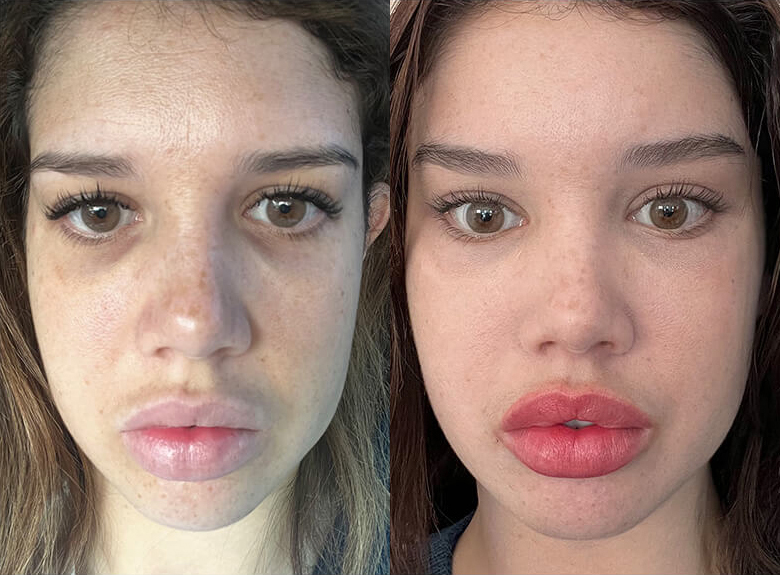

Recovery after fat grafting isn’t immediate, and results don’t show right away. Swelling and bruising are normal at first, especially in areas like the face, and this can make things look fuller or uneven early on. During the first few days, the fat doesn't have a blood supply yet and survives by pulling oxygen and nutrients from the surrounding tissue.

Over the next few weeks, your body starts growing new blood vessels into the fat graft. Fat that successfully connects will stay (like 50-70% when done professionally), while fat that doesn’t is slowly absorbed. As swelling goes down, the area softens and the final result becomes clearer.

Recovery after fat grafting isn’t immediate, and results don’t show right away. Swelling and bruising are normal at first, especially in areas like the face, and this can make things look fuller or uneven early on. During the first few days, the fat doesn't have a blood supply yet and survives by pulling oxygen and nutrients from the surrounding tissue.

Over the next few weeks, your body starts growing new blood vessels into the fat graft. Fat that successfully connects will stay (like 50-70% when done professionally), while fat that doesn’t is slowly absorbed. As swelling goes down, the area softens and the final result becomes clearer.